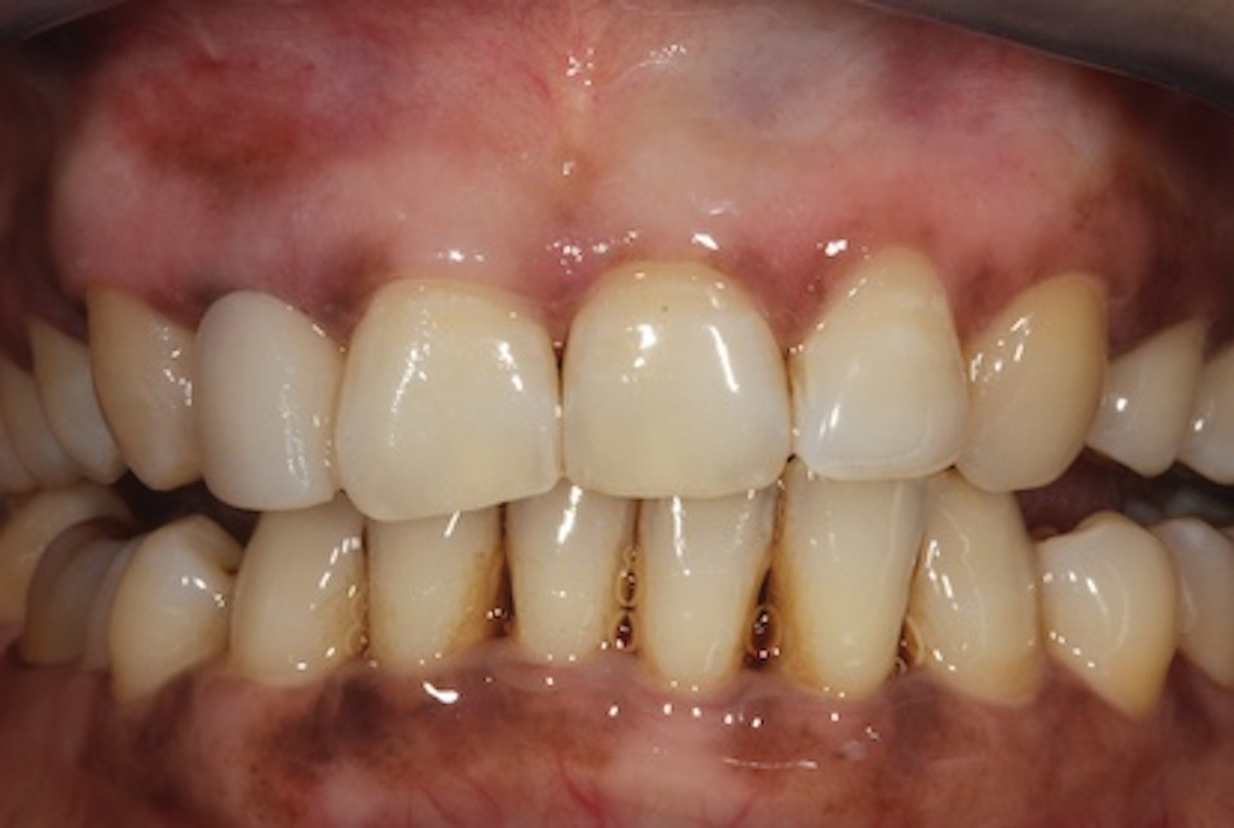

(13.) Immediate posttreatment view of the final fiber-reinforced composite bridge.

Figure 13

Continue developing the pontic by layering it with an appropriately selected shade of composite to create an esthetic, well-matched restoration. The degree of layering performed will depend on the esthetic demands of the case and the preferences of the operator. To safeguard the tissues and prevent contamination of the pontic site, the final finishing and shaping of the bridge should be performed before removal of the rubber dam (Figure 12). Any final occlusal adjustments should be performed after rubber dam removal (Figure 13).